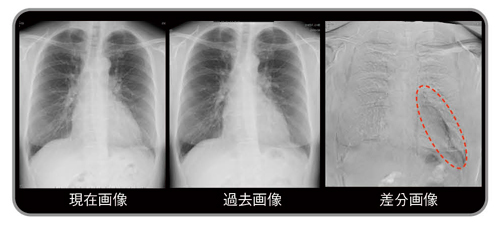

現在画像と過去画像は,被写体の撮影体位(前後屈,側屈)や息止めの位相の違いで,被写体全体の位置や血管・骨などの各臓器の位置が一致しないため,単純な差分処理では位置ずれアーチファクト(偽像)が発生しやすい。アーチファクトが生じると,経時的変化のある部分の検出が困難となる。ワーピング処理(図2,3)は,現在画像の対応位置に一致するように,過去画像を局所領域ごとに変形させてから差分する方法で,アーチファクトが大幅に軽減する。

図3 経時差分の実際

a:現在画像 b:過去画像

c:単純差分画像

d:ワーピング処理後差分画像。cに比べ,鎖骨,肋骨,心血管のアーチファクトが消失し,右下肺野の新たに出現した病変のみが明瞭に描出されている(←)